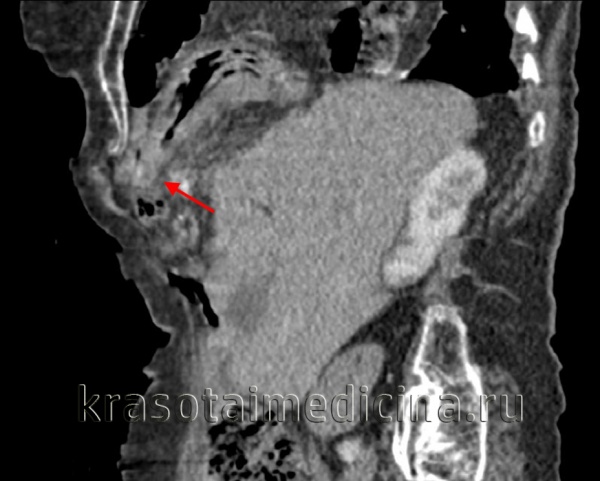

- Лучевая диагностика. Выполняется рентгенография и КТ грудной полости, КТ брюшной полости. Выявить разрыв на рентгенограмме можно только при пролапсе органов пищеварения в область грудной клетки. Для уточнения локализации травматического дефекта грудобрюшной перегородки, дифференциальной диагностики травмы и релаксации органа осуществляется контрастная рентгенография желудка либо ирригография. Просматривается желудок или петли кишечника в левой половине грудной клетки, определяется смещение пищевода.

КТ органов грудной клетки/брюшной полости. Травматический дефект в передних отделах диафрагмы справа с эвентрацией кишечника, сальника, кровеносных сосудов в грудную полость